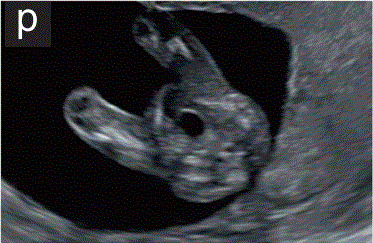

7.1.3  到妊娠12周时,胎儿膀胱在下腹部正中可见低回声圆形结构,纵向直径<为7mm(图2p和2q)。

图2 11+0至14+0周时,可作为详细胎儿超声检查的一部分获得的解剖图。

(p)胎儿骨盆的横断切面,显示存在胎儿膀胱。

(q)胎儿腹部矢状面图,显示胎儿膀胱、生殖器结节、膈肌和脊柱。在该胎龄时,对胎儿膀胱的任何测量都应在纵向和矢状面上进行。

10.1 对外生殖器和胎儿性别的评估是基于在矢状面的方向的生殖器结节(图2q)。